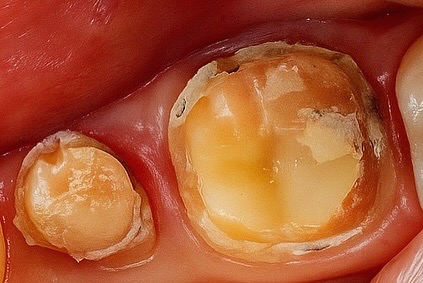

The patient presented with a grossly decayed mandibular premolar (Fig 1). Clinical and radiographic evaluation revealed pulpal necrosis and compromised coronal walls but sufficient root length for retention.

- Fig 1: Pre-operative view showing extensive coronal destruction.